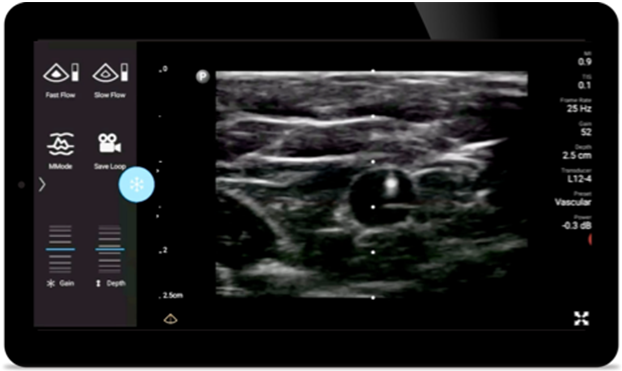

Reduzca las complicaciones en procedimientos guiados por aguja

El ultrasonido portátil Lumify para anestesiología le ayuda a visualizar claramente la definición de los bordes con la colocación de la aguja, los nervios circundantes, los vasos sanguíneos y los planos fasciales.